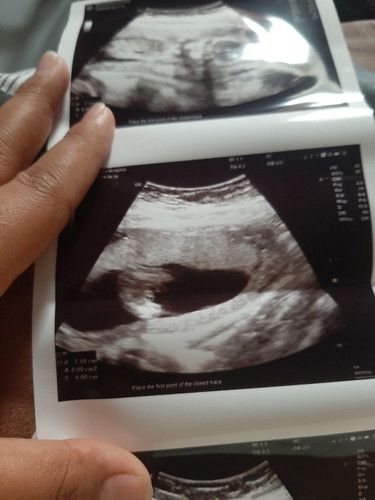

หมอบอกผู้ชาย100%รูปนี้ตอน16วีคตอน20วีคก็มีค่ะแต่เป็นวีดีโอหมอก็ยังบอกผู้ชาย100%ตอนนี้28วีคอยากซื้อของไว้แล้วค่ะอยากถามความคิดเห็นแม่ๆว่าชาย100%มั้ยคะ